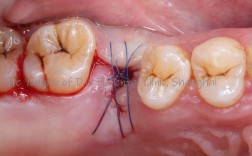

(图片来源网络,侵删)- 这是最常见的方式,医生会使用可吸收缝线(如羊肠线、PGA线等,无需拆线)或不可吸收缝线(需要拆线),将牙龈切口边缘对齐缝合,完全覆盖种植体和手术区域。

- 当牙龈组织张力较大时,医生可能会采用更复杂的缝合技术(如“8”字缝合、水平褥式缝合、松弛切口等)来分散张力,确保伤口能无张力或低张力愈合。